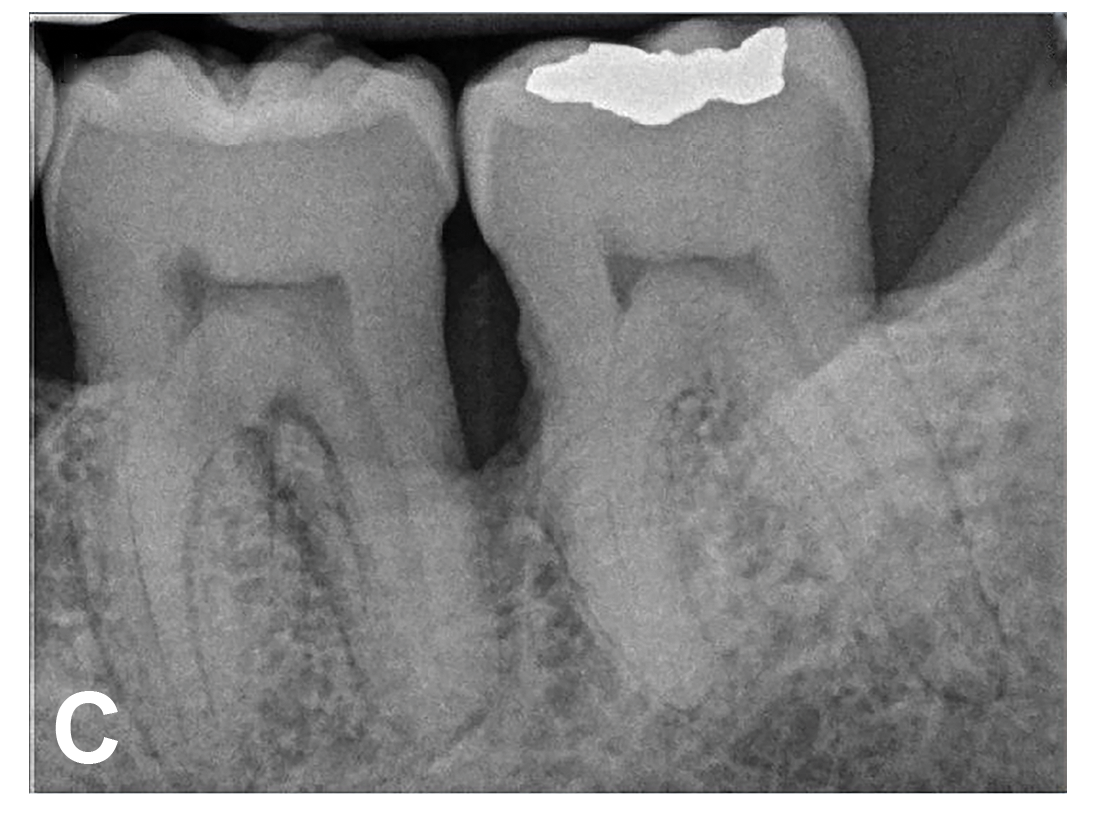

(7.) Progressive improvement in bone quality, quantity, and morphology during each time period, especially in the furcation area of tooth No. 18, which shows a noticeable narrowing of the width of the bony defects, slight apical resorption of the distal root of tooth No. 18, and the encasing of residual cementum on the distal root of No. 19 by new bone formation. Periapical radiographs were taken of teeth Nos. 17, 18, and 19 on June 25, 2016, January 28, 2017, August 23, 2019, and September 4, 2020, respectively, the final of which was taken after almost 5 years post-initial scaling and root planing and alternating supportive periodontal maintenance.

Figure 7

(8.) Progressive improvement in bone quality, quantity, and morphology during each time period, especially in the furcation area of tooth No. 18, which shows a noticeable narrowing of the width of the bony defects, slight apical resorption of the distal root of tooth No. 18, and the encasing of residual cementum on the distal root of No. 19 by new bone formation. Periapical radiographs were taken of teeth Nos. 17, 18, and 19 on June 25, 2016, January 28, 2017, August 23, 2019, and September 4, 2020, respectively, the final of which was taken after almost 5 years post-initial scaling and root planing and alternating supportive periodontal maintenance.

Figure 8

(9.) Progressive improvement in bone quality, quantity, and morphology during each time period, especially in the furcation area of tooth No. 18, which shows a noticeable narrowing of the width of the bony defects, slight apical resorption of the distal root of tooth No. 18, and the encasing of residual cementum on the distal root of No. 19 by new bone formation. Periapical radiographs were taken of teeth Nos. 17, 18, and 19 on June 25, 2016, January 28, 2017, August 23, 2019, and September 4, 2020, respectively, the final of which was taken after almost 5 years post-initial scaling and root planing and alternating supportive periodontal maintenance.

Figure 9

(10.) Progressive improvement in bone quality, quantity, and morphology during each time period, especially in the furcation area of tooth No. 18, which shows a noticeable narrowing of the width of the bony defects, slight apical resorption of the distal root of tooth No. 18, and the encasing of residual cementum on the distal root of No. 19 by new bone formation. Periapical radiographs were taken of teeth Nos. 17, 18, and 19 on June 25, 2016, January 28, 2017, August 23, 2019, and September 4, 2020, respectively, the final of which was taken after almost 5 years post-initial scaling and root planing and alternating supportive periodontal maintenance.

Figure 10

The patient's periodontal disease improved with initial nonsurgical periodontal therapy that involved scaling and root planing. This initial treatment was followed by only SPT every 3 months. Despite treatment, residual deep periodontal probing depths remained, so a decision was made to maximize improvements with nonsurgical therapy and to reassess as needed to determine whether surgical intervention was appropriate. After almost 5 years of SPT and good patient compliance with plaque control and supportive care, the periodontium was stable. Because of the resulting bone formation and improvements in clinical attachment levels (Figure 7 through Figure 13), it was determined that periodontal surgical intervention was not necessary.

In the case report presented, treatment with nonsurgical therapy for 5 years effectively halted destruction and led to bone regeneration and improved clinical attachment levels. Although the primary etiology of periodontal disease is well documented, secondary etiologic and contributing factors are numerous.16 After initial therapy in the current case, there was radiographic evidence of a hypercementosis-like lesion on the distal root of tooth No. 19 (Figure 7 through Figure 10). Hypercementosis is a nidus for plaque accumulation leading to disease progression; however, the presence of this lesion did not explain the disease severity observed for tooth No. 18. Chronic periodontitis is the most widespread form of periodontal disease, and nonsurgical periodontal therapy is the most common type of therapy.17 Scaling and root planning is the gold standard for periodontal treatment. When performed meticulously, they result in improvement of clinical parameters through changes related to tissue shrinkage, long junctional epithelium, new attachment, and in rare circumstances, regeneration.18 The use of nonsurgical periodontal therapy for treatment of periodontal disease requires that the timing for re-evaluation is customized for each patient. Because individuals heal at different rates, the overall medical condition, nutritional intake, environmental and social risks factors, local factors, and colonization of pathogenic bacteria of patients should be considered.7,8 Some patients cannot afford, or choose not to pursue, surgical periodontal therapy. For these patients, clinicians should delay surgical decisions until periodontal risk factors are addressed and nonsurgical efforts are exhausted.

Although rare, the radiographic evidence in the current case indicated that nonsurgical therapy effectively halted the destructive effects of severe chronic periodontitis and led to bone regeneration, thereby eliminating the need for surgery. The current case also showed that nonsurgical periodontal therapy may lead to desirable outcomes for patients with severe chronic periodontal disease if the patient is compliant with plaque control, supportive periodontal therapy is provided, etiological and risk factors are eliminated, and the body is given adequate time to heal.11 An additional factor that may have influenced the positive outcome of the current case was the patient's favorable health status.